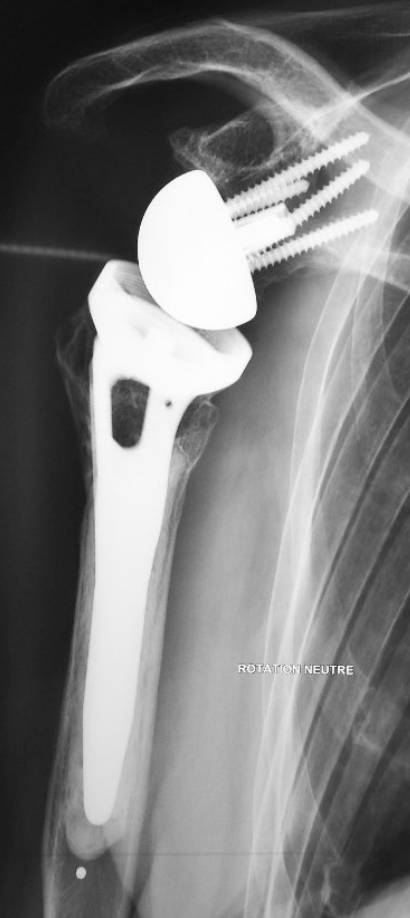

Enfin, il arrive que la fracture soit trop sévère pour conserver l’articulation. Chez les personnes âgées notamment, une indication de prothèse spéciale pour fracture peut s’avérer nécessaire.

Le traitement varie en fonction de la gravité de la fracture, de l'âge du patient, de ses antécédents médicaux et chirurgicaux, ainsi que de ses besoins fonctionnels. Pour les fractures moins sévères, une immobilisation avec une attelle ou un coussin peut suffire. Cette méthode conservatrice est accompagnée d'un traitement contre la douleur et de conseils pour limiter l'hématome et la douleur, comme l'application de glace. Pour les fractures plus complexes, une intervention chirurgicale peut être nécessaire pour fixer les fragments osseux avec du matériel d'ostéosynthèse. Dans certains cas, notamment chez les patients âgés avec des fractures sévères, la pose d'une prothèse spéciale pour fracture peut être la meilleure option.